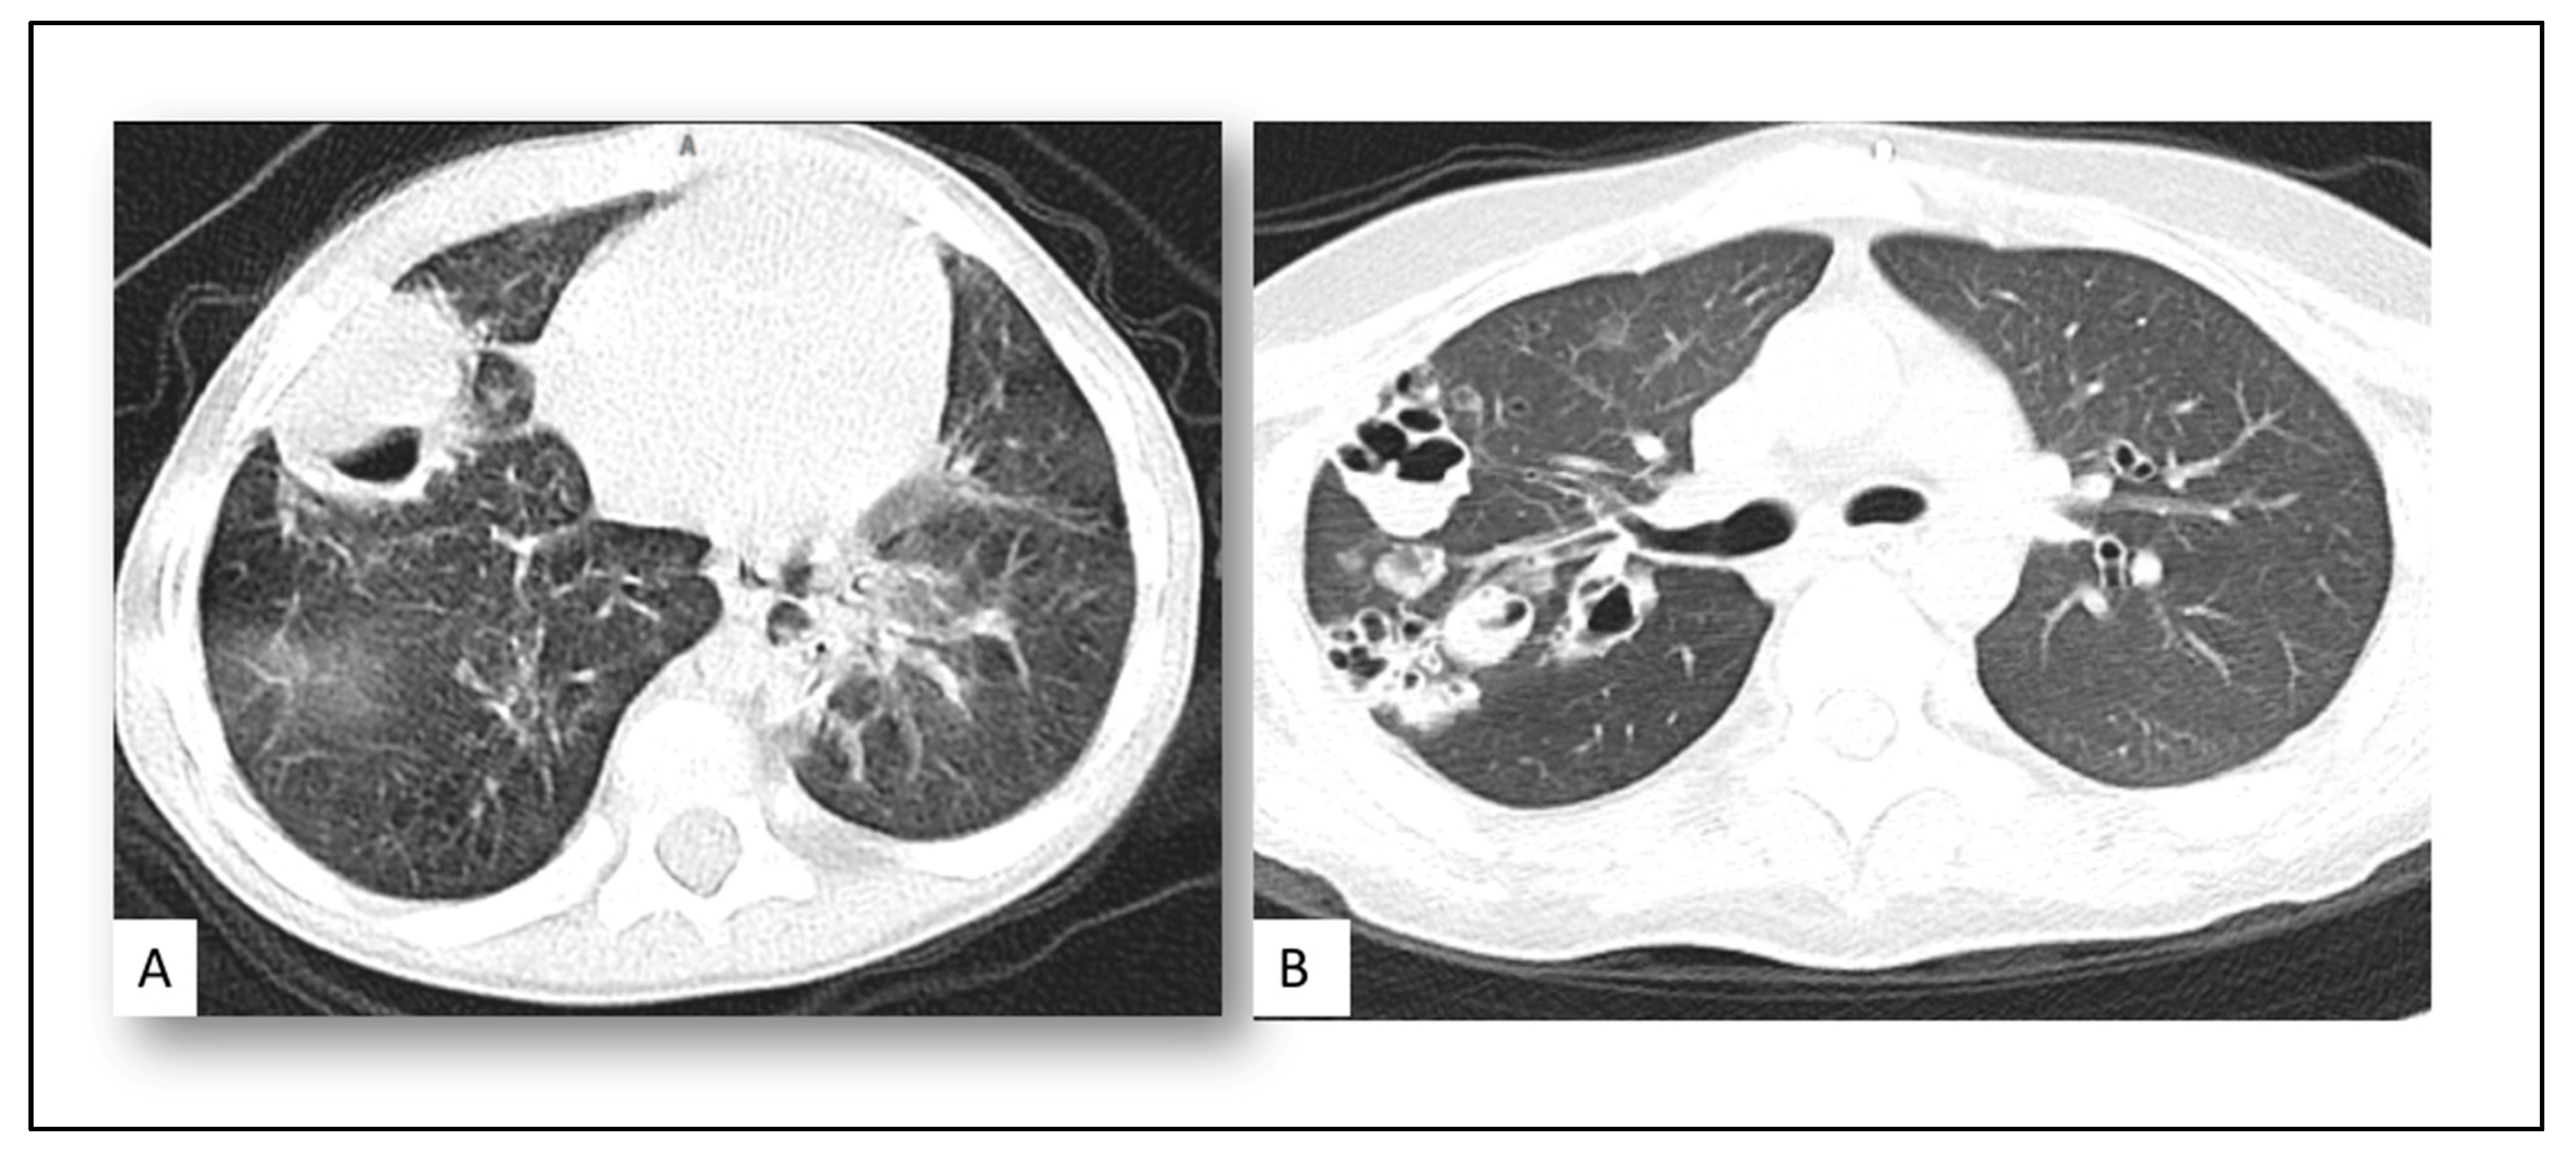

| - Pulmonary nodule with halo sign | 11 (52%) |

| - Pyramidal consolidation patch | 4 (20%) |

| - Cavitary lung lesion | 6 (28%) |